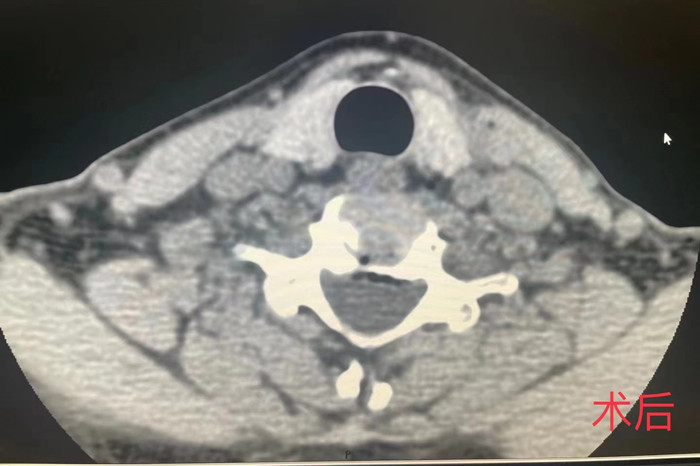

近日,我院疼痛科在南区影像科的配合下,成功开展了首例CT介导经皮穿刺颈椎间盘等离子射频髓核消融手术。

手术由安徽医科大学第一附属医院疼痛科主任王立奎和我院疼痛科副主任耿天勇共同主刀,在南区影像科医师的密切配合下,通过CT引导的精准定位,将细至0.9毫米的等离子射频针穿刺进入患者的病变椎间盘,成功对病灶部位进行射频消融,手术历时1小时左右。术后患者双上肢疼痛麻木即得到明显改善。